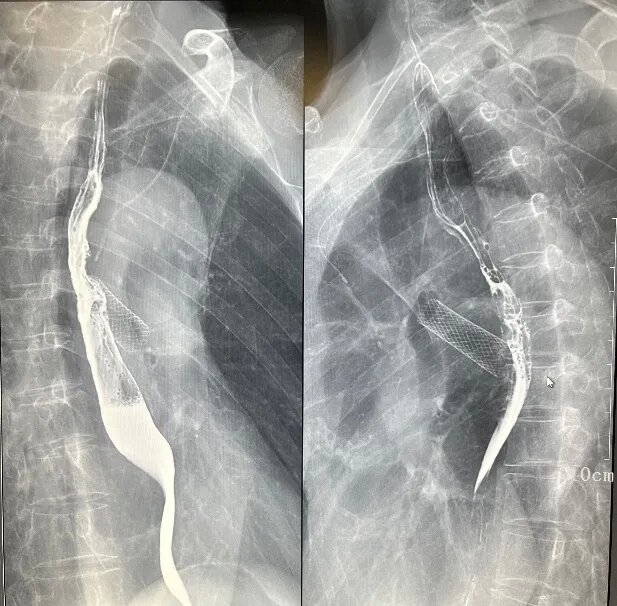

(一)食道钡剂造影

三、介入诊疗

如胆道造影、T管造影、ERCP,支持简单的介入治疗。